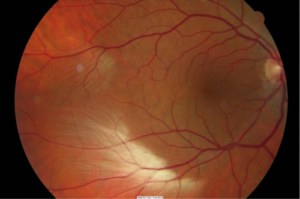

软性渗出需要与正常眼底的视网膜有髓神经纤维相鉴别。

▲ 图示有髓神经纤维。